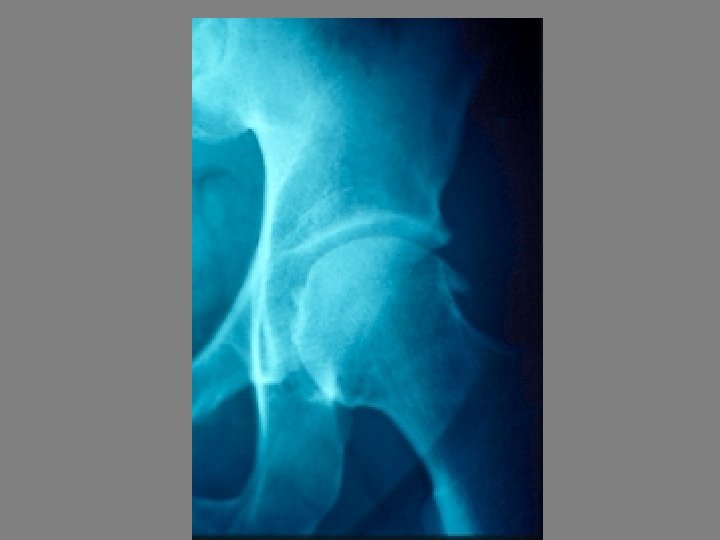

SEMIOLOGIE DE LA HANCHE J-P ESCHARD • Anatomie Articulation profonde Articulation très emboîtée mobilité

SEMIOLOGIE DE LA HANCHE J-P ESCHARD • Anatomie Articulation profonde Articulation très emboîtée mobilité réduite

SEMIOLOGIE DE LA HANCHE 3°Signes d’examen (signes physiques): Etude des mouvements Mouvements passifs+++: le

SEMIOLOGIE DE LA HANCHE 3°Signes d’examen (signes physiques): Etude des mouvements Mouvements passifs+++: le coxogramme Mouvements combinés Mouvements actifs

SEMIOLOGIE DE LA HANCHE 3°Signes d’examen (signes physiques): Etude des mouvements Mouvements passifs+++: le coxogramme flexion/extension/abduction/adduction RE/RI Mouvements combinés Mouvements actifs : étude des muscles et des tendons: le moyen fessier++ 4° Examen régional: neurologique amyotrophie